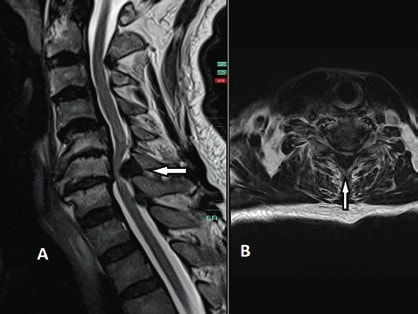

Bei anamnestischem und klinischem Verdacht auf traumatische Rückenmarkläsionen erfolgt in der Regel als erste diagnostische Methode eine CT-Untersuchung der Wirbelsäule auf Höhe der vermuteten Läsionssegmente zum Ausschluss oder zur Darstellung möglicher Frakturen und Dislokationen. Bei jüngeren Patienten kann die CT-Untersuchung beim Beweis einer dislozierten Fraktur, die zur klinisch vermuteten Rückenmarkläsion passt, ausreichend sein. Jedoch empfiehlt sich bei älteren Patienten – trotz im CT nachgewiesener dislozierter Fraktur – die Durchführung einer zusätzlichen MRT-Untersuchung der Läsionshöhe und der benachbarten Segmente zur genaueren Darstellung möglicher degenerativer kompressiver Veränderungen der Wirbelsäule auf Höhe der benachbarten Segmente, welche die Therapieentscheidung und das Therapieausmaß entscheidend beeinflussen können.

Bei fehlendem Nachweis einer knöchernen kompressiven Verletzung der Wirbelsäule durch die CT-Untersuchung ist es obligat, eine ergänzende notfallmäßige MRT-Untersuchung der klinisch vermuteten Läsionshöhe durchzuführen. Ergänzend sollten eine Farbduplexsonografie und gegebenenfalls – bei fehlenden Kontrastmittelkontraindikationen – eine CT-Angiografie der Aa. vertebrales bei lateralen Wirbelkörper- oder Wirbelbogenfrakturen der Halswirbelsäule zum Ausschluss einer Dissektion erfolgen. Zudem sind die Verletzungen der inneren Organe bei Verlust der Schmerzwahrnehmung im Falle einer Querschnittläsion schwierig zu diagnostizieren; daher ist eine schnelle orientierende Sonografie von Thorax und Abdomen bei Traumapatienten von großer Bedeutung, um mögliche innere Blutungen auszuschließen, zumal die Sonografie weder zeitaufwendig noch strahlenbelastend ist.